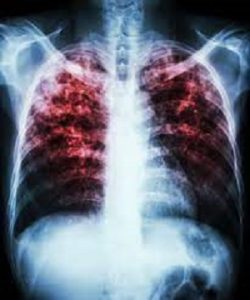

इंदौर। टीबी के मरीजों (TB patients) को दवाई (Medicines) के साथ-साथ पोषण भी दिलाने के लिए भारत सरकार (Govt. Of India) द्वारा शुरू की गई निक्षय मित्र अभियान इंदौर में भी जोरदार से शुरू हो चुका है। शहर के कई संस्थानों सहित समाजसेवियों ने हजारों मरीजों को जहां गोद लेने की तैयारी कर ली है, वहीं विभाग टीबी को खत्म करने के लिए वृहद रूप से अभियान छेड़ रहा है।

भारत सरकार द्वारा टीबी के मरीजों को गोद लेकर टीबी मुक्त बनाने की पहल रंग लाने लगी है। इंदौर के समाजसेवियों सहित उद्योगपतियों ने टीबी के मरीजों को गोद लेने के लिए आगे हाथ बढ़ाए हैं। स्वास्थ्य विभाग द्वारा जहां ऐसे मरीजों की सूची मुहैया कराई जा रही है, वहीं पोषण और स्वास्थ्य के लिए जरूरी दवाइयों और भोजन की सूची भी दी जा रही है। ज्ञात हो कि टीबी के देश को 2025 तक टीबी मुक्त कराने के लिए प्रधानमंत्री नरेंद्र मोदी ने निक्षय मित्र अभियान शुरू किया है। इसमें देशभर के 13.5 लाख मरीजों को गोद देने की प्रक्रिया शुरू कर दी गई है। अब तक 9 लाख से अधिक मरीजों को देश स्तर पर गोद दिया जा चुका है। इंदौर में भी इस प्रक्रिया में जोर पकड़ा है। टीबी विभाग के विशेषज्ञ डा. सलील भार्गव ने जानकारी देते हुए बताया कि कोई भी आम व्यक्ति आकर इन मरीजों को गोद लेने की प्रक्रिया में शामिल हो सकता है। इसके लिए दवाइयों का खर्च सरकार उठाती है। पोषण के लिए पोष्टिक आहार का खर्च गोद लेने वाले आवेदक को उठाना होगा। विभाग ने शहर के सर्भी क्षेत्रों में टीबी की जांचों के साथ साथ अवेरनेस प्रोग्राम भी छेड़ रखे हैं, जिसके लिए विभाग समय-समय पर नुक्कड़ नाटक और जागरूकता अभियान चला रहा है।